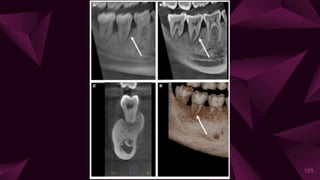

⩥ Two-dimensional modalities

⩥ Volumetric modalities (three dimensional)

⊳ Panoramic tomosynthesis

⊳ Cone-beam computed tomography

104